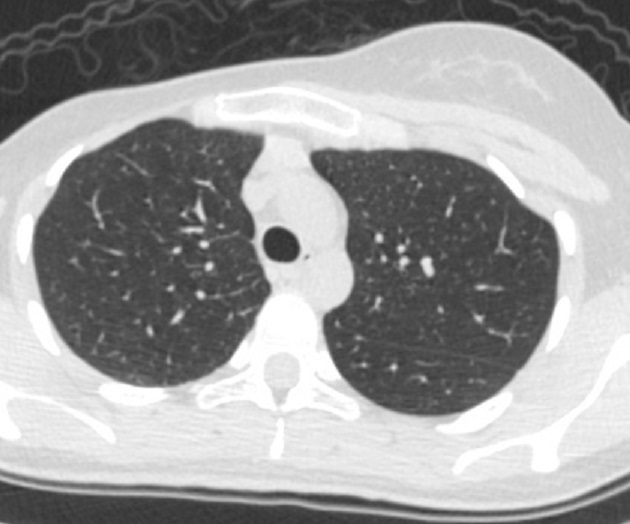

|

Et en fenêtre parenchymateuse ... |